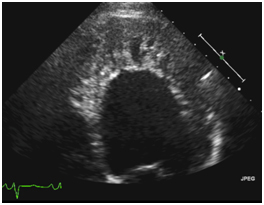

Also known as “isolated non-compaction of the left ventricular myocardium” or “spongiform cardiomyopathy,” it is primarily caused by the abnormal embryonic development of the heart muscle. In left ventricular noncompaction (LVNC), there is retarded myocardial morphogenesis and persistence of the trabecular meshwork (B). Left ventricular noncompaction is a rare unclassified cardiomyopathy with markedly prominent apical trabeculae with deep intertrabecular recesses (Fig.

Enjoy the videos and music you love, upload original content, and share it all with friends, family, and the world on YouTube. Left ventricular noncompaction (LVNC) is a cardiomyopathy associated with sporadic or familial disease, the latter having an autosomal dominant mode of transmission. Echocardiographic short axis apical views of the left ventricle in a patient with non-compaction cardiomyopathy and a G4.5 mutation.

Genetics, Clinical Features, and Long-Term Outcome of Noncompaction Cardiomyopathy. Echocardiograms were matched for patients with and without a clinical diagnosis of LVNC. Left ventricular non-compaction, the most recently classified form of cardiomyopathy, is characterised by abnormal trabeculations in the left ventricle, most frequently at the apex.

This gives the left ventricle a 'spongy' look (a bit like honeycomb). As normal development progresses, these trabeculated structures undergo significant compaction that transforms them from spongy to solid. These are best visualized on color flow Doppler of the left ventricle using apical windows.

Left ventricular non compaction (LVNC) is a type of cardiomyopathy which is characterized by the presence of prominent trabeculations in the left ventricle with deep recesses between the trabeculations and a thin compacted myocardial layer. A series of 15 cases. Noncompaction of the ventricular myocardium:.

Non-compaction cardiomyopathy, is a rare congenital cardiomyopathy that affects both children and adults. Apical 4 chamber view shows multiple trabeculations and deep recesses at the ventricular apex. However, there are still many unknowns regarding its etiology and pathology, but also the.